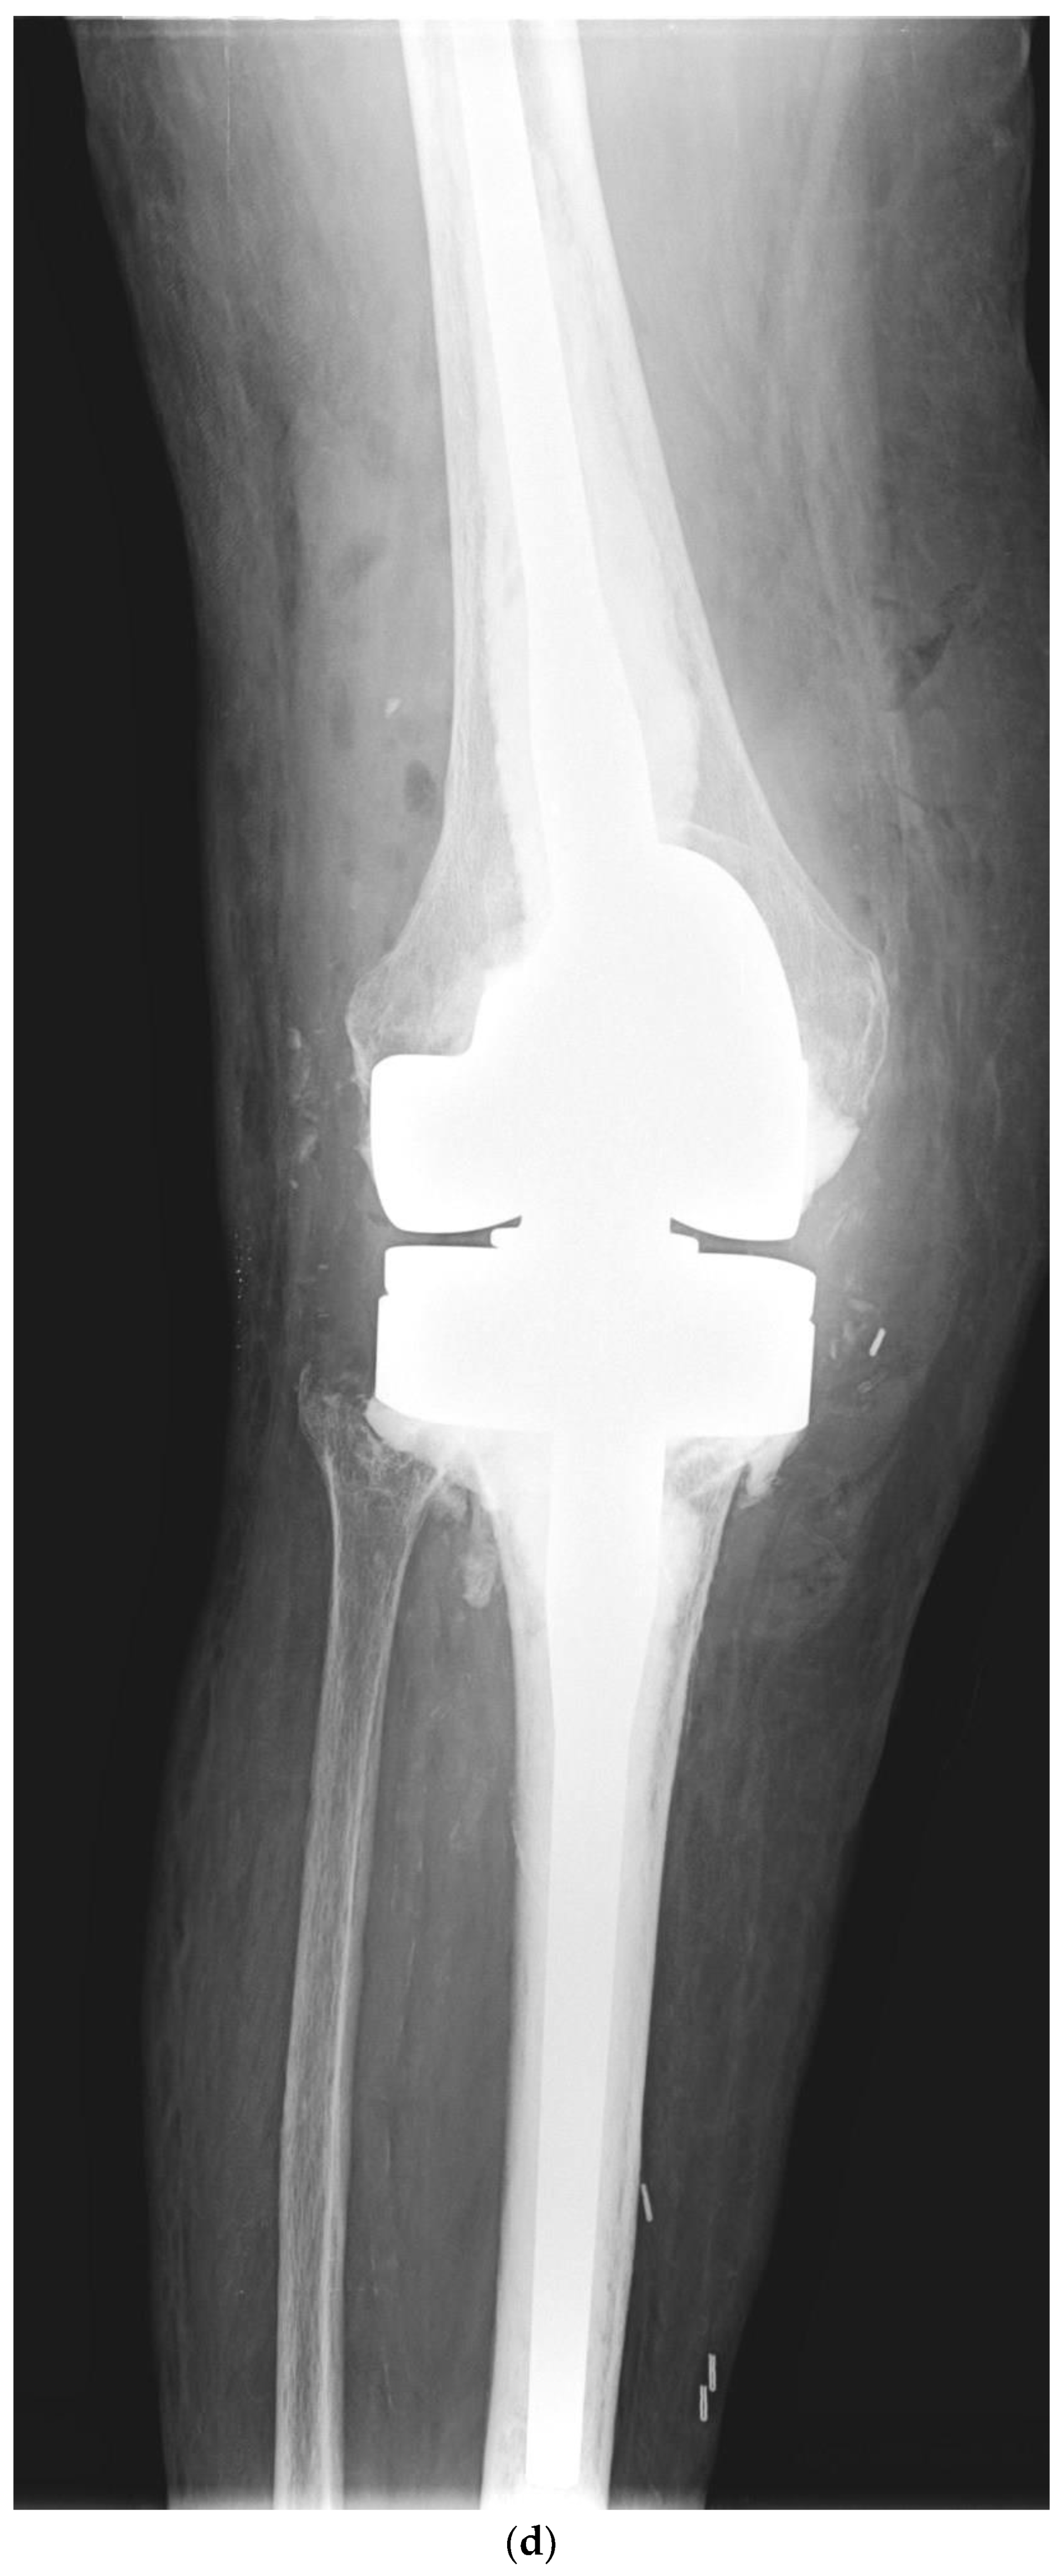

Risk Factors for Periprosthetic Joint Infection after Primary Total Knee Arthroplasty